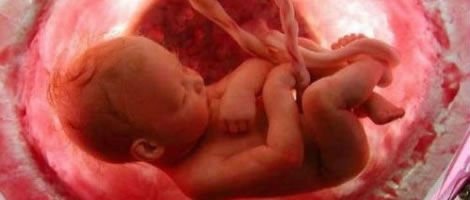

Os músculos do bebé já estão formados e, graças ao comprimento do cordão umbilical, este já se pode mover com mais energia.

O futuro ser também responde aos estímulos do exterior como a música. O bebé mede aproximadamente de entre 27 a 32cm e pesa de entre 450 a 750 gramas.

A pele do bebé começa a ficar opaca e mais consistente e este já pode abrir e fechar os olhos. As proporções do copo do bebé começam a igualarem-se as da sua cabeça. O feto cada vez mais se parece com um recém-nascido.